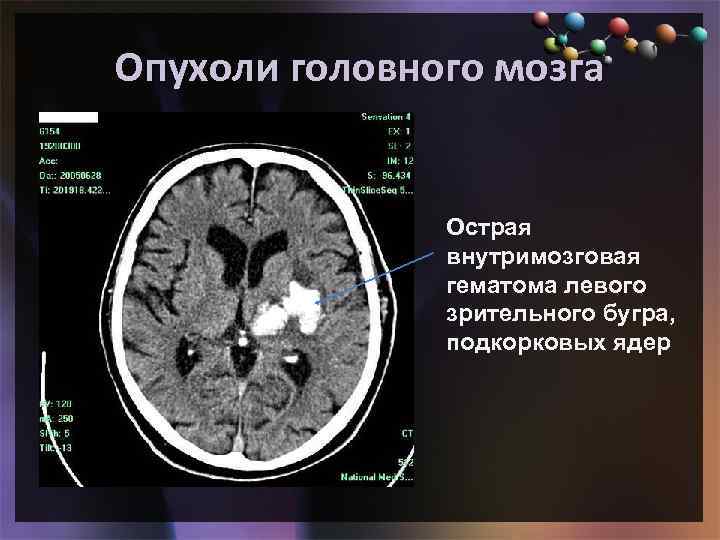

Опухоли головного мозга • Подзаголовок слайда Острая внутримозговая гематома левого зрительного бугра, подкорковых ядер

Опухоли головного мозга • Подзаголовок слайда Острая внутримозговая гематома левого зрительного бугра, подкорковых ядер